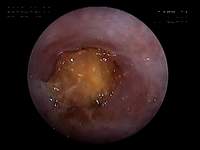

お正月に庭石を食べたというご連絡 がありました(10kgのワンちゃん)。数日経っても便に出てこなく、嘔吐があったとのことでした。X線を撮ってもまだ胃内にあるのが確認されたため、内視鏡を実施しました。胃内の十二指腸につながる通路にはまっていました(写真)。ワイヤーで引いても引き出すことが困難だったため、このあと手術にて摘出しました。

幽門洞にはまっている庭石を

ワイヤーでとらえようとする様子